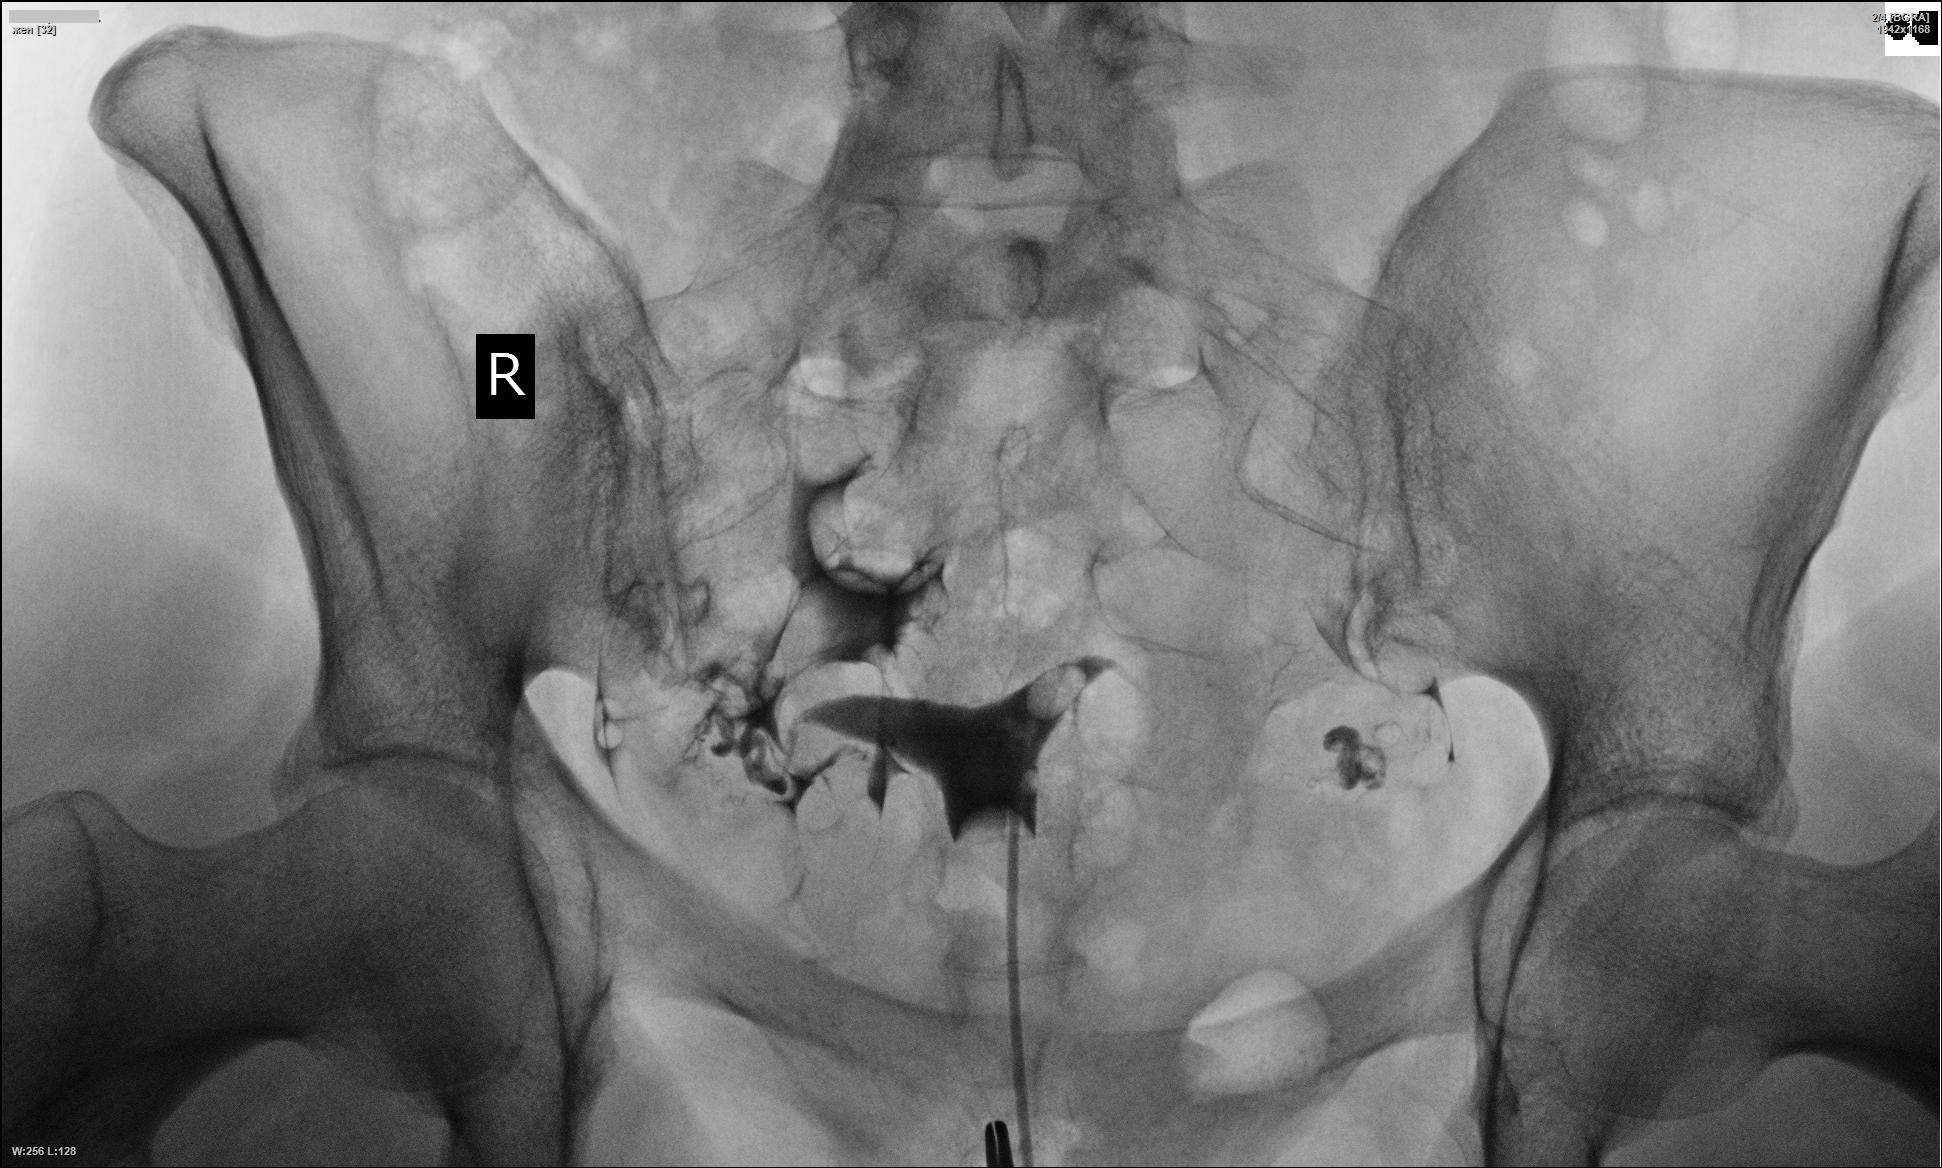

Медицинские снимки: Проходимость маточных труб

Раздел: Кадры-подсказки